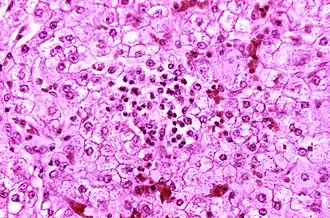

La maladie provoque une stéatose hépatique avec une inflammation minimale et une encéphalopathie sévère (avec gonflement du cerveau). L'ictère n'est pas habituellement présent. Le foie peut devenir légèrement agrandi et ferme, et l'apparence des reins se modifie.

- Anomalie hépatique avec une stéatose microvésiculaire à la ponction/biopsie hépatique dont le mécanisme est imparfaitement élucidé. Les autres atteintes hépatiques se caractérisent par une ammoniémie élevée (concentration importante en NH3/NH4+ dans le sang) et une cytolyse hépatique légère avec des alanine aminotransférases(ALAT) à trois fois la normale ;